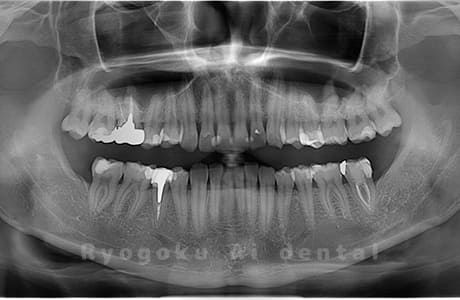

Case02

-

- 原因

- 下顎の水平埋伏智歯

- 治療内容

- 下顎の水平埋伏智歯を抜歯

<リスク・副作用>

手術後は痛み、腫れ、痺れなどの副作用が生じる場合があります。